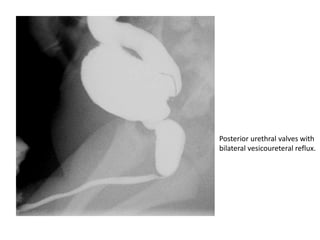

• Posterior Urethral Valves

• The most common congenital obstructive

lesion of the urethra, occurring only in

phenotypic boys.

• Posterior urethral valves result from the

formation of a thick, valvelike membrane from

tissue of wolffian duct origin that courses

obliquely from the verumontanum to the

most distal portion of the prostatic urethra

• VCUG is the best imaging technique for the

diagnosis of posterior urethral valves.

• Radiologic findings include dilatation and

elongation of the posterior urethra and,

occasionally, a linear radiolucent band

corresponding to the valve.

• The bladder neck becomes hypertrophic and

appears narrow in relation to the dilated

posterior urethra.

• VUR occurs in 50% of patients.

• Bladder trabeculation, hypertrophy, and

diverticula are also demonstrated at VCUG

Posterior urethral valves with

bilateral vesicoureteral reflux.